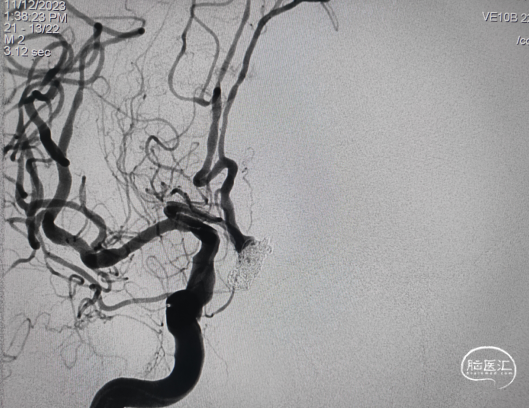

术后正侧位,动脉瘤栓塞满意,载瘤动脉血流通畅,未行支架或微导管辅助栓塞。

术后撤出通路导管,停止麻醉,神志逐渐转清,言语欠佳,肢体活动较前略好转。术后复查颅脑CT平扫示纵裂出血较前无明显变化。